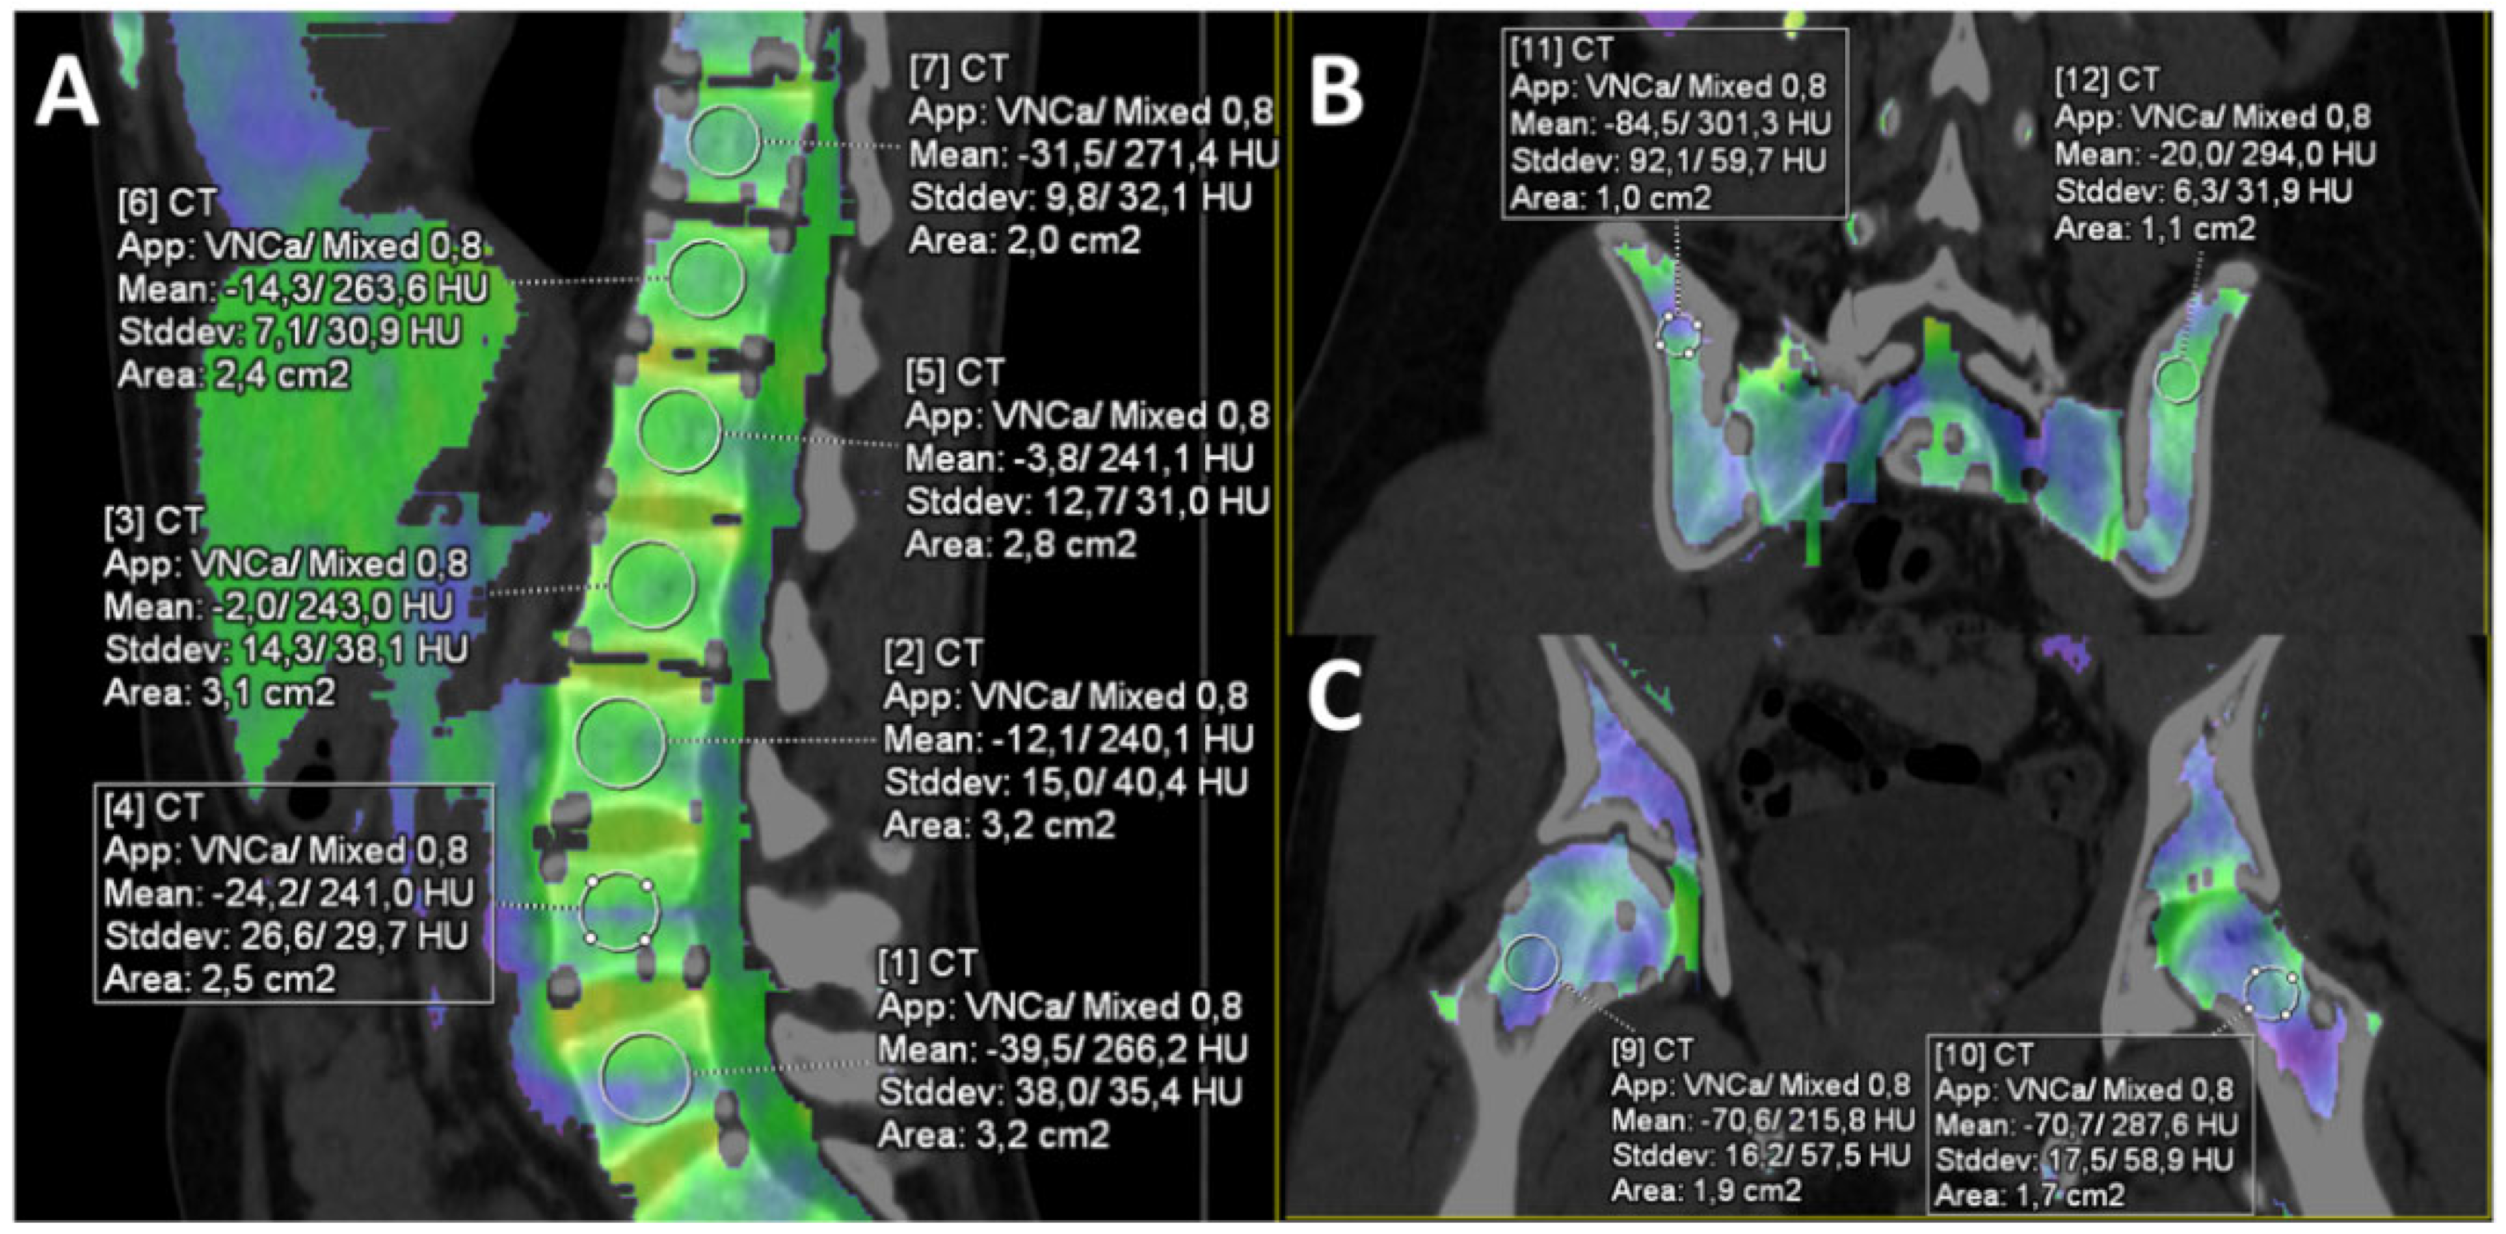

2.2. Computed Tomography Protocol and Post-Processing

2.3. Image Analysis